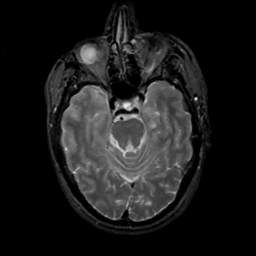

MR Study #12, May 12, 1991 -- Slice #17